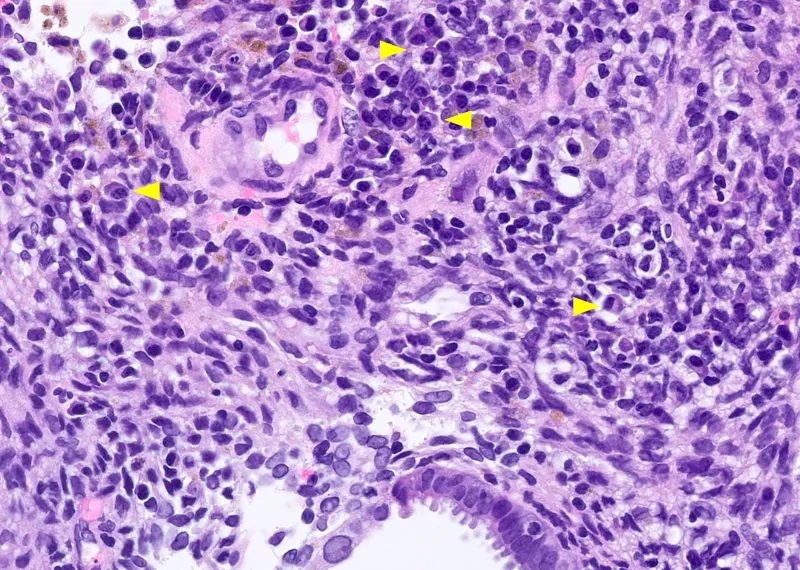

- Chronic Endometritis

- Key: Plasma cells in endometrial stroma (diagnostic hallmark).

- Causes: Pelvic Inflammatory Disease (PID), Tuberculosis (TB), IUD, retained products of conception. 📌

- Tuberculous Endometritis (subtype): Caseating granulomas, acid-fast bacilli; common cause of infertility in India.

⭐ Plasma cells in endometrial stroma are the hallmark of chronic endometritis.